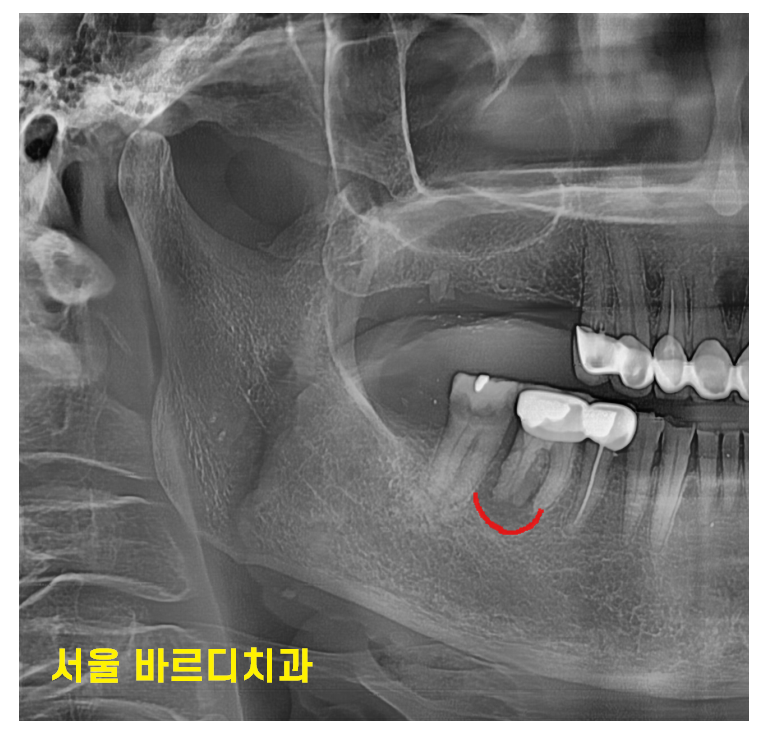

처음 오셨을때 윗니 어금니 6개가 빠져있었는데요.

양쪽 작은 어금니 1개로 식사를 하고 계셨습니다.

아래 치아도 염증도 있고

목 부분이 부러져 건들 건들거리는 상황

230728 부러져서 흔들거리는 상황